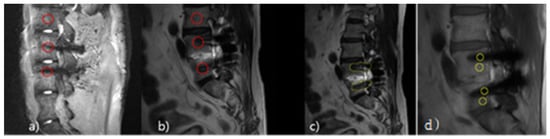

:1. Introduction

2.2. Process of Producing Phantom

2.3. Analysis Method

2.3.1. Quantitative Analysis Method

2.3.2. Qualitative Analysis Method